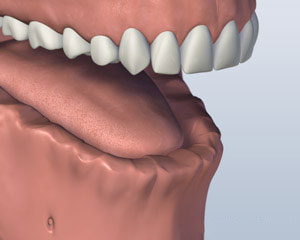

螺杆保留义齿

第三种选择包括将五个或更多的植入物在你的下巴和安装永久假牙. 假牙代替由它固定在支撑柱或棒螺钉或扣环举行. 它不接触牙龈组织, 它可以让你的假牙清洁下而不删除它. 这假牙将替换所有丢失的下齿,除了在维护访问将不会被删除. 虽然清洁假牙下,而不移除它耗费更多的时间和需要更多的灵活性, 谁想要一个永久性的义齿很多患者喜欢这个选项.

1. 之前

2. 植入放置

3. 义齿附